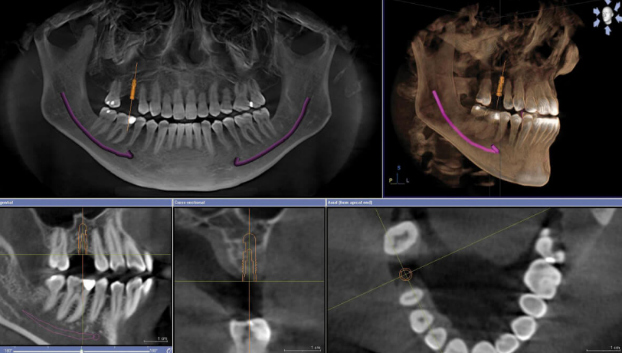

- Maxillary sinus evaluation:

- Assessment of sinus floor morphology

- Maintenance of at least 1mm clearance unless performing a sinus lift

- Consideration of septa and other anatomical variations